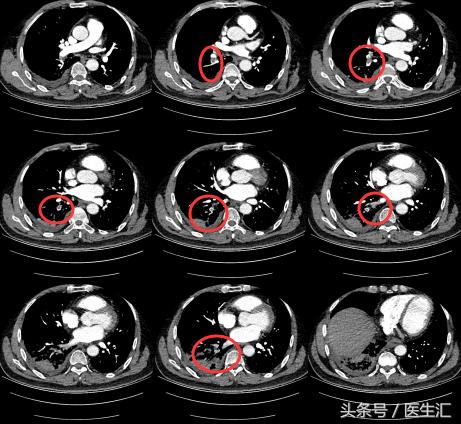

【关注】

每一个层面都有肺动脉的充盈缺损。

为明确患者肺栓塞的原因,所以做了彩超,结果如下图: